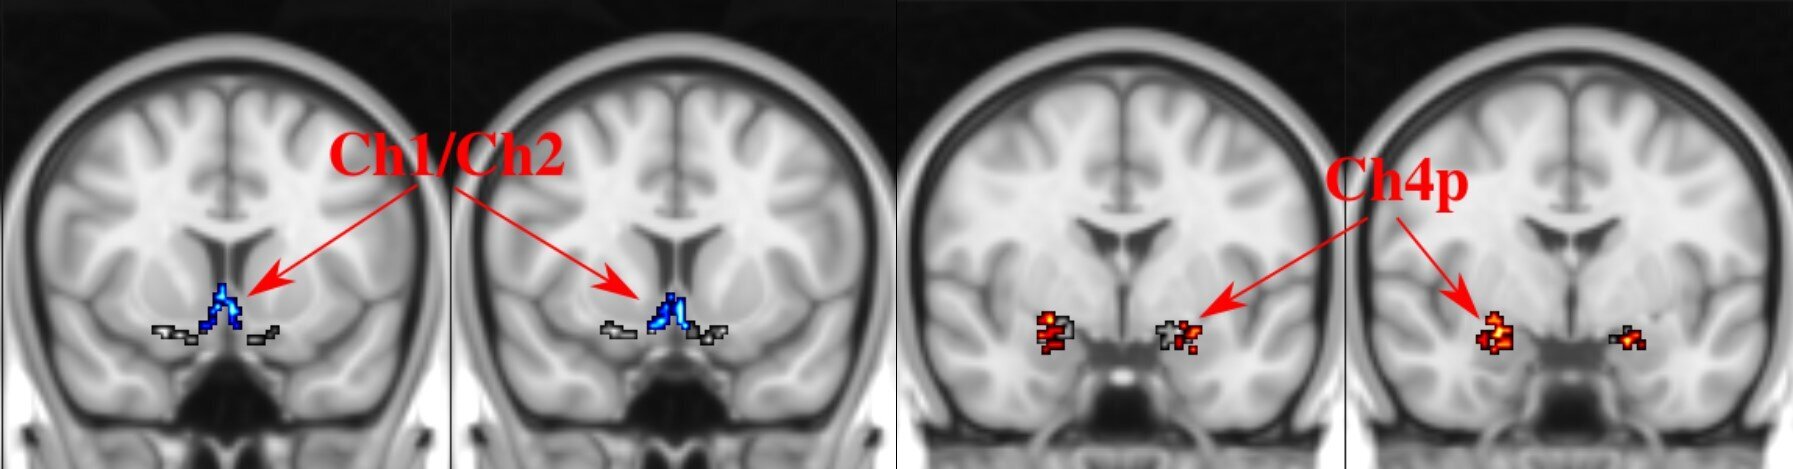

Болезнь Альцгеймера — самая распространенная форма деменции, от которой ежедневно диагностируют 250 человек в Австралии. Ученые из национального научного агентства CSIRO изучили данные 475 человек с разной степенью когнитивных нарушений. Было обнаружено, что ухудшение работы определенной области мозга связано с наличием болезни Альцгеймера еще до появления симптомов.